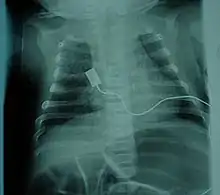

X-ray showing bell-shaped torso due to atrophy of intercostal muscles and using abdominal muscles to breathe. Bell-shaped torso is not specific to individuals with SMA.

• Bell-shaped torso (caused by using only abdominal muscles for respiration) in severe SMA type